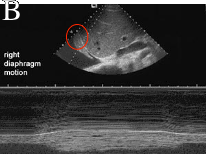

These two images are from a study called a 'sniff test'. This is done to document motion of the diaphragms. Image A shows the left diaphragm, which has the detector overlying it (oval). When the patient sniffs, the graph at the bottom shows normal motion. Image B shows no motion, or paralysis.